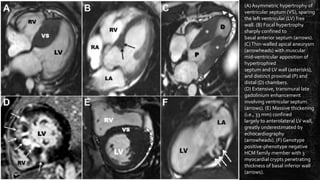

(A) Asymmetric hypertrophy of

ventricular septum (VS), sparing

the left ventricular (LV) free

wall. (B) Focal hypertrophy

sharply confined to

basal anterior septum (arrows).

(C)Thin-walled apical aneurysm

(arrowheads) with muscular

mid-ventricular apposition of

hypertrophied

septum and LV wall (asterisks),

and distinct proximal (P) and

distal (D) chambers.

(D) Extensive, transmural late

gadolinium enhancement

involving ventricular septum

(arrows). (E) Massive thickening

(i.e., 33 mm) confined

largely to anterolateral LV wall,

greatly underestimated by

echocardiography

(arrowheads). (F) Genotype

positive-phenotype negative

HCM family member with 3

myocardial crypts penetrating

thickness of basal inferior wall

(arrows).